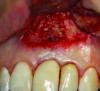

Patient 1: A 30-year-old female patient with an unremarkable medical history presented with implant No. 9 exhibiting retrograde peri-implantitis. Tooth No. 9 had been replaced with the implant 8 years prior because of a history of trauma and failed root canal treatment. The implant exhibited a periapical radiolucency with the sinus tract tracing to the apex of implant No. 9 (Figure 1 and Figure 2). The patient had a high smile line with longer clinical crowns at Nos. 9 and 10 compared with Nos. 7 and 8 (Figure 1 and Figure 2).

Fig 1 and Fig 2. Case 1: Initial clinical presentation with gutta-percha placed in the apical fistula of tooth No. 9 (Fig 1); radiograph showing gutta-percha point leading to the periapical lesion (Fig 2).